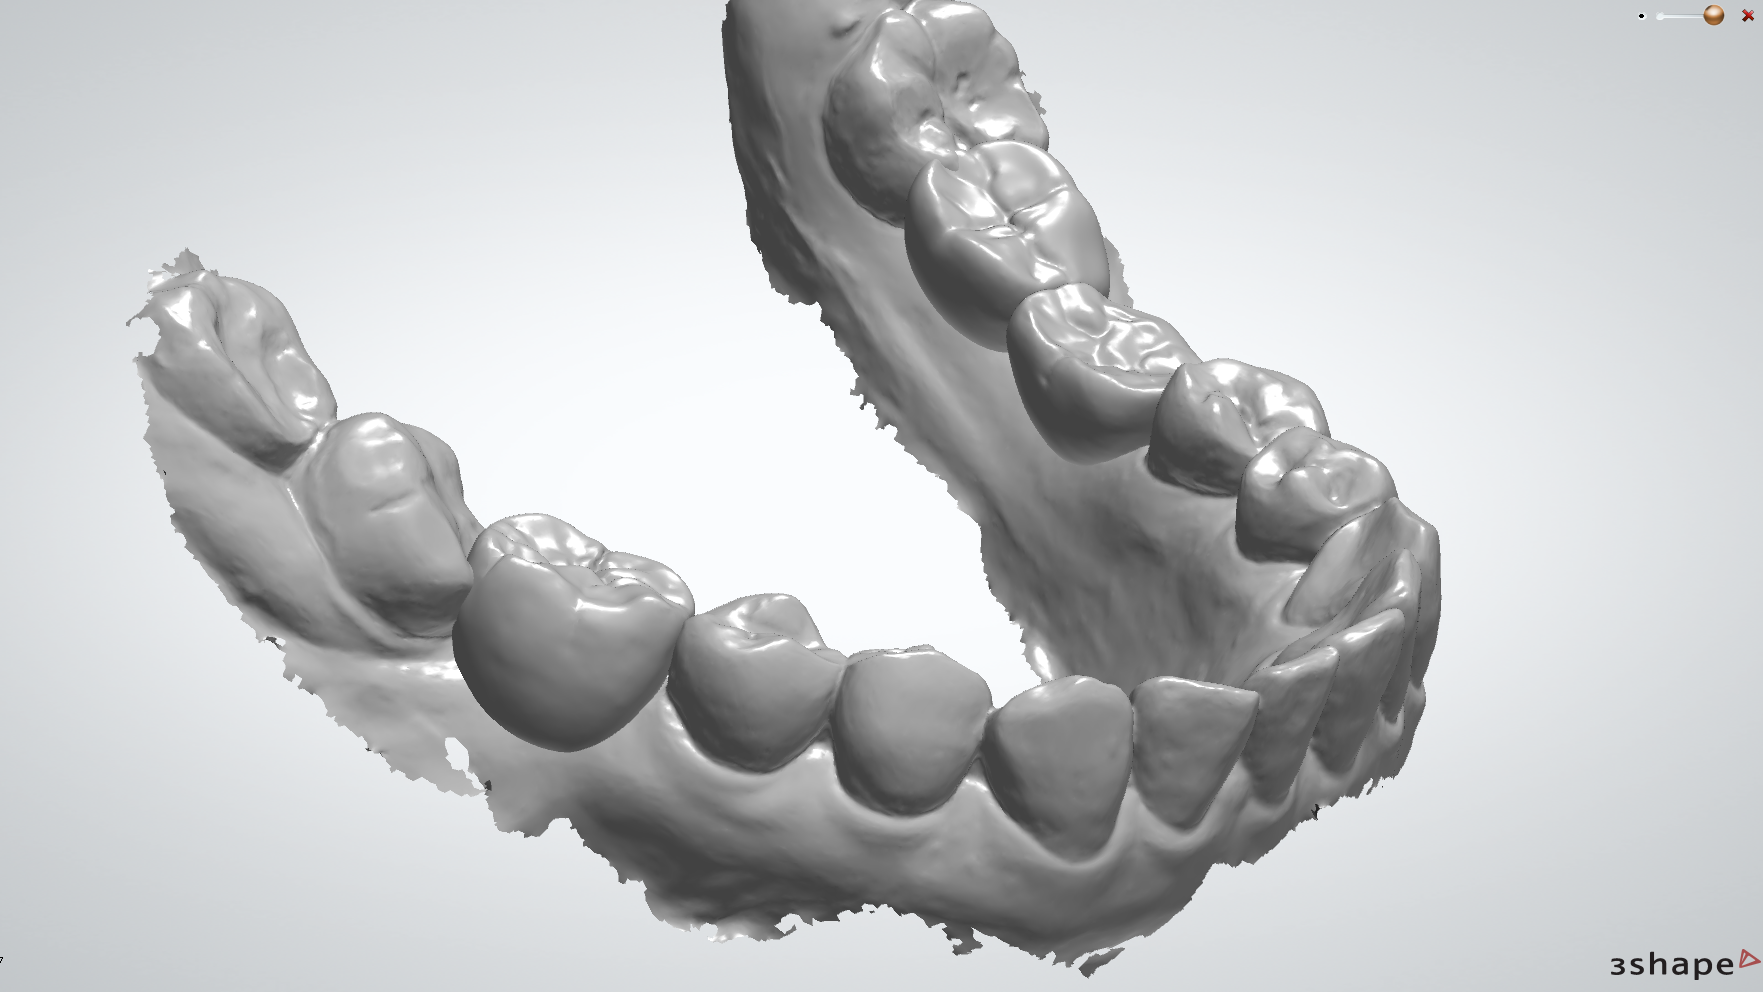

導航植牙,也叫做「4D動態導航植牙」,其實就是利用高科技來幫助我們更精準地完成植牙手術,簡單來說,就是在手術前會先幫你做電腦斷層(CT)、數位口腔印模,把你的骨頭、神經、血管、口腔等重要結構都看得很清楚,然後用電腦軟體中預先規劃未來假牙位置、植體植入的深度及角度,模擬出植牙的最佳路徑做定位,降低植牙療程中的誤差,有效提高治療的成功率並減少植牙後遺症,達到真正的數位植牙。

數位植牙利用先進的數位科技,通過口內掃描、治療規劃、植體植入手術和假牙製作等流程,將整個植牙過程進行數位化。

| 丹麥3shape口內掃描機 取代傳統印模方式,降低印模時的不適感,將口內缺齒情形以3D清楚呈現。 |